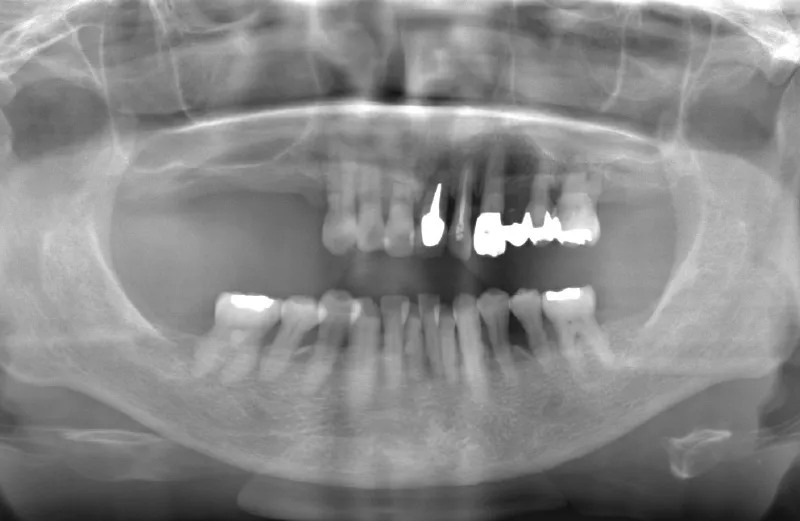

メガジェンオペの症例紹介04

治療前

治療後

| 主訴 | 他院では左上6左下6右上567の根が割れているのと、虫歯が深く保存できないと言われた。 残っている骨の状態が悪く、上顎洞までの垂直骨量が不足しているので抜歯後しばらく待ってからサイナスリフトが必須であり、インプラント治療に1.5年かかると言われたのでセカンドオピニオンを希望で来院。入れ歯は嫌でどうにか短期間で噛めるようにインプラントでの治療を希望している。 |

|---|---|

| 治療期間 | 2.5ヶ月で仮歯が入り、 4ヶ月で最終補綴物が入って終了。 |

| 治療費 | 約2,000,000円 |

| 治療内容 | 上顎にはエクストラワイドショートインプラントを埋入し、上顎洞を移植材を用いずに挙上しインプラントを埋入した。約2.5ヶ月で仮歯を装着し、様々な機能面に問題がないことを確認し4ヶ月で最終補綴物を装着して終了した。 |

| 治療の リスク |

インプラント埋入オペ時に術者が上顎洞内にインプラントを迷入させる可能性がある。これは術者が技術的に熟練していれば防ぐことが可能。 |